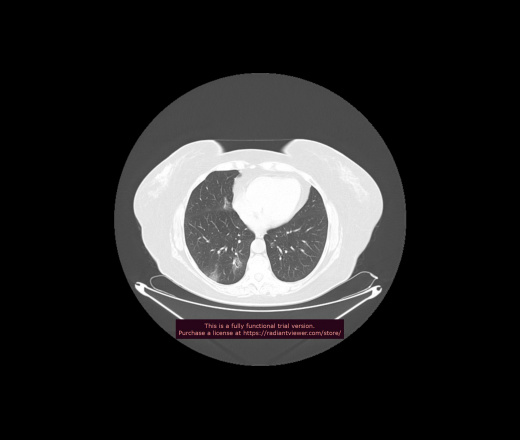

Уважаемые коллеги, если имеется интерес, сможете ли Вы спрогнозировать дальнейшее +-одинаковое течение процесса у 4 данных разных пациентов? Зацепиться где-то можно очень просто, где-то нельзя.